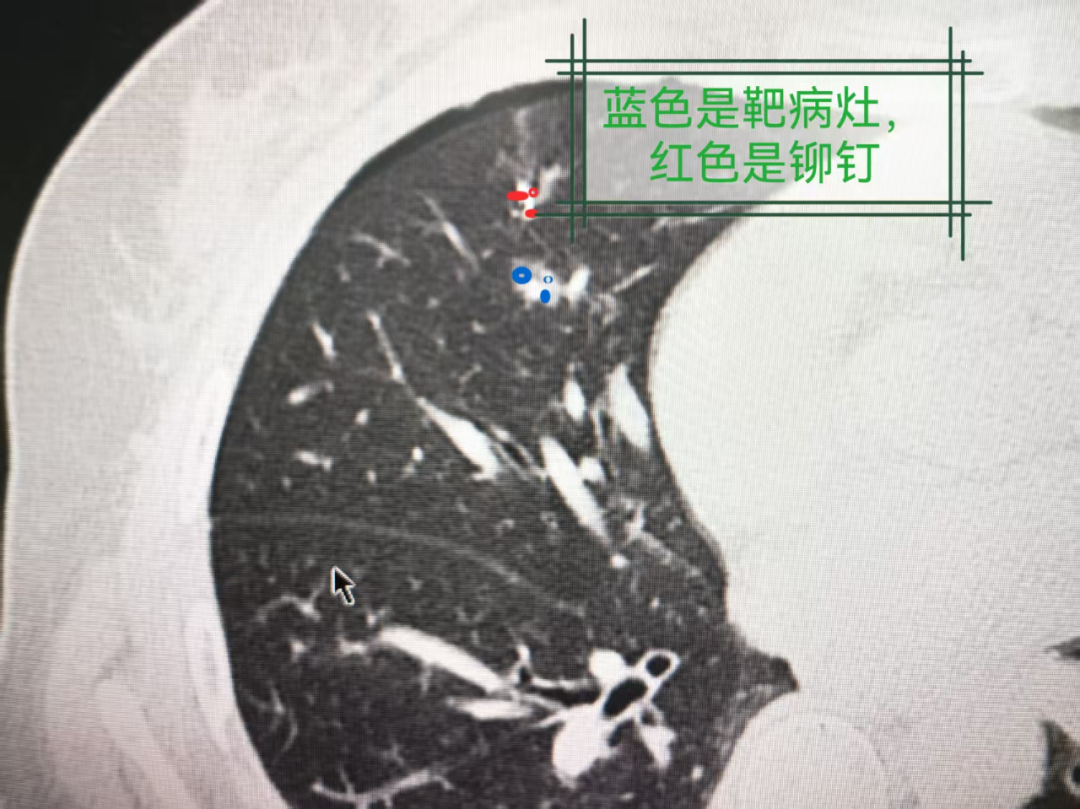

简单来说,精准定位就是在手术前,通过CT引导将特殊的“定位铆钉”(类似微小标记物)精准植入结节所在的肺组织,为外科医生标记出病灶的“精确坐标”。

图1:CT影像中定位针的走向示意图